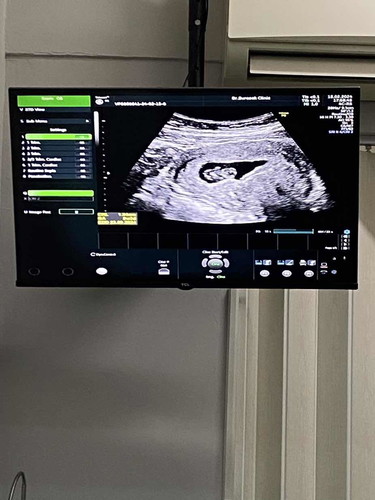

8W3D♥️ ทีมคลอดกันยา

เดือนที่แล้วมาไม่เจออะไรเลย ไม่เจอถุงตั้งครรภ์ หมอบอกอาจจะท้องอ่อนยังไม่ถึง5วีคเลยไม่เจอ รอบนี้มาได้เจอกันแล้วนะคะน้องได้8w3dมีหัวใจเต้นแล้ว ลุงหมอบอกหนูเหมือนลูกหมีแพนด้าคะ ขอเป็นกำลังใจให้คุณแม่ที่ยังไม่เจอน้องนะคะ อดทนริอีกหน่อยเดี๋ยวก็ได้เจอคะ🥰🥰♥️